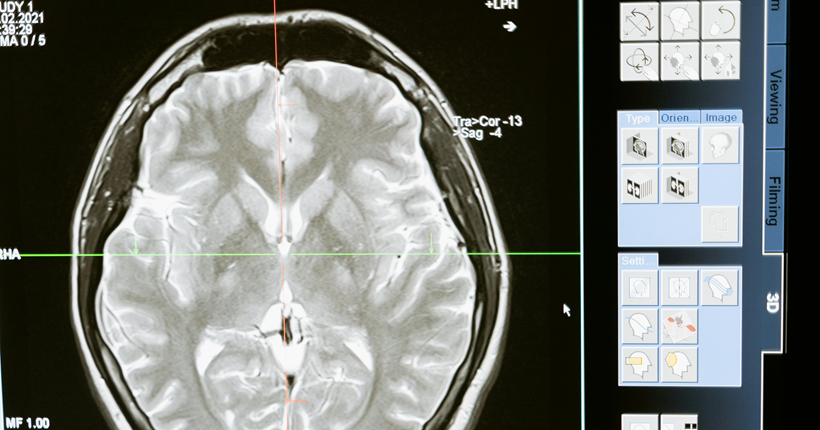

El dolor representa un problema no resuelto en las personas mayores, particularmente en aquellas con demencia. Debido al envejecimiento poblacional, y la asociación de esta patología neurodegenerativa con la edad, actualmente observamos un incremento en este grupo de pacientes. Además, las personas con demencia son más propensas a experimentarlo debido a la coexistencia de deterioro cognitivo con otras entidades clínicas de tipo crónico. A su vez, la dificultad para expresarlo de forma verbal que presentan estas personas, como resultado de la evolución de la demencia, acentúa la complejidad del abordaje del dolor, materializándose esta, específicamente, en que la valoración del dolor en personas con deterioro cognitivo es, a menudo, inadecuada.

La imposibilidad de autoreporte de la experiencia dolorosa propia de los pacientes con demencia avanzada impide la utilización de los autoinformes, instrumentos considerados como la medida más fiable y afinada para contrastar la existencia e intensidad del dolor siempre que la persona no presente dificultades de comunicación y/o sea capaz de recordar, entender y responder sobre su experiencia dolorosa.

En este contexto, la observación conductual de la persona con demencia avanzada como alternativa para valorar el dolor a través del reconocimiento de cambios comportamentales ha conllevado a la confección de hasta 24 escalas, aunque no todas están disponibles en español por no haber sido adaptadas culturalmente y validadas a este idioma. Entre todas las escalas, la Pain Assessment in Advanced Dementia Scale (Painad), concretamente, por su sencillez y sus propiedades psicométricas, las cuales avalan su validez y fiabilidad, se postula como una herramienta prometedora para minimizar el infradiagnostico e infratatamiento del dolor en las personas con demencia.